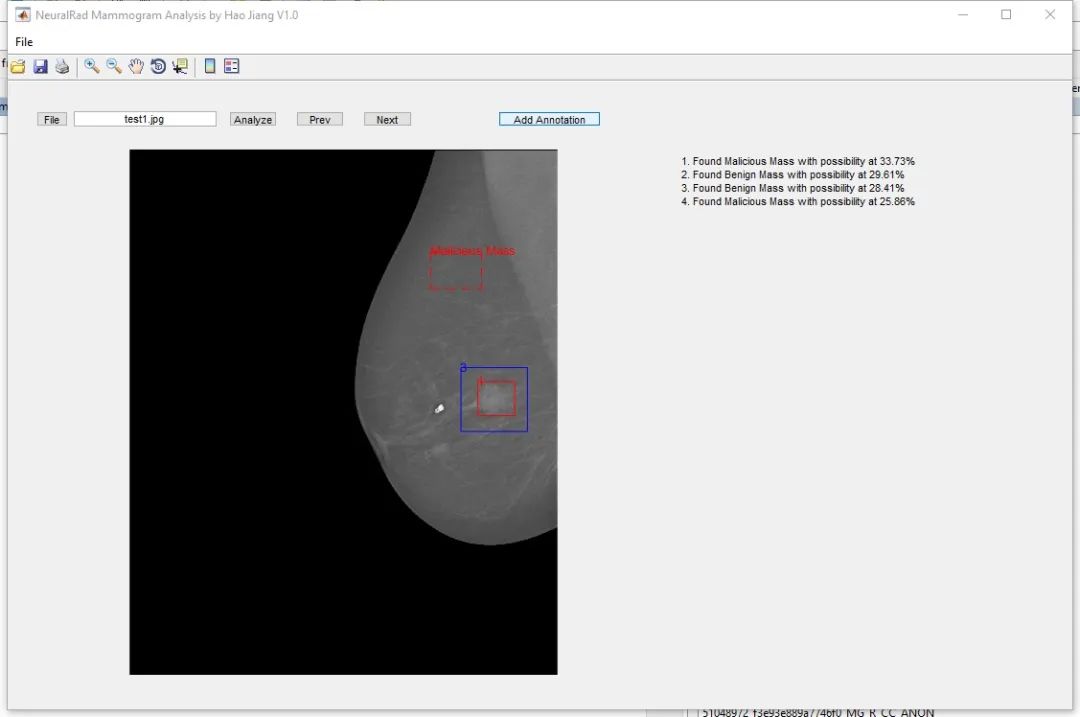

2018 年,一位名叫 coolwulf 的楼主开了个帖子,说自己做了一个网站。

用户只要上传自己的 X 光影像图片,就能让 AI 为自己快速诊断乳腺癌病情,肿瘤识别的准确率,也已经达到 90%。

简单来说,就是让人工智能帮你“ 看片子 ”,准确率还几近媲美专业医生,并且完全免费。

这个免费的 AI 检测乳腺癌网站,coolwulf 前后大概花了三个月的业余时间,忙得时候直接睡在办公室,最后终于在 2018 年上线。

除了网站,

当时还有个桌面版的检测软件 ▼